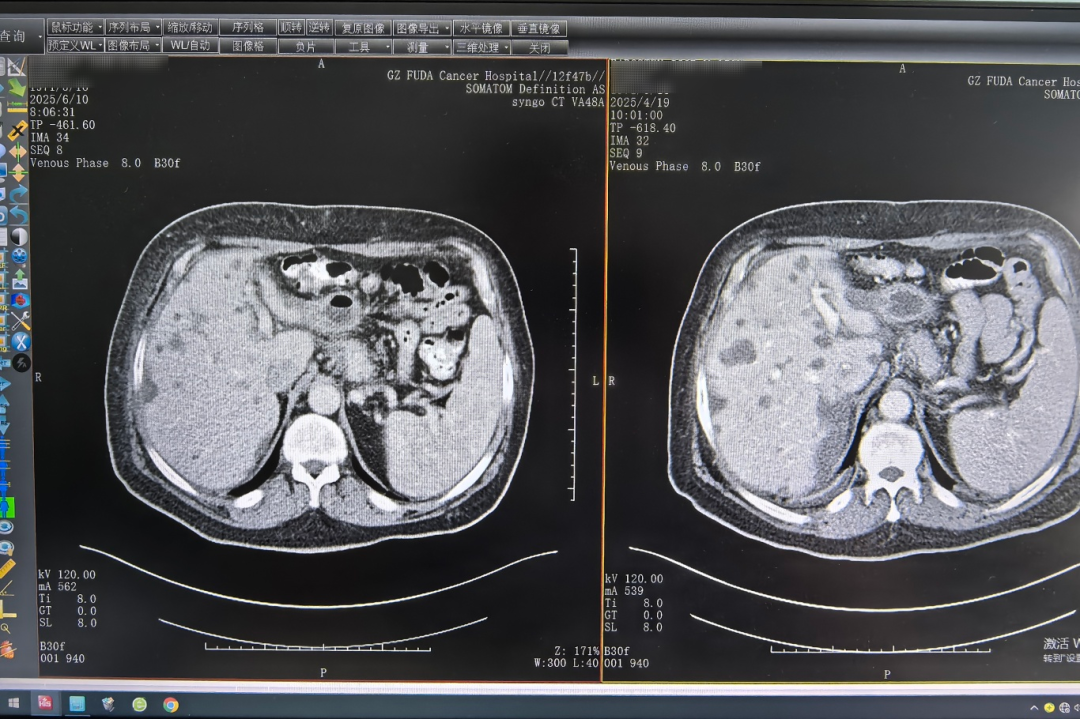

在首次接受免疫和靶向治疗后,伊戈尔感到他的肝痛得到了显著缓解。两三个疗程后CT影像提示:胰腺病灶、肝脏多发转移瘤较前缩小。医疗四科团队立马根据其身体状况,及时调整治疗方案,为其施行肝脏肿瘤冷冻消融术,即在影像设备的引导下,经皮把消融针直接穿到肝脏肿瘤内,通过快速冷冻和复温循环,精准灭活肿瘤细胞。

△左图为6月10日影像结果,右图为4月19日影像结果